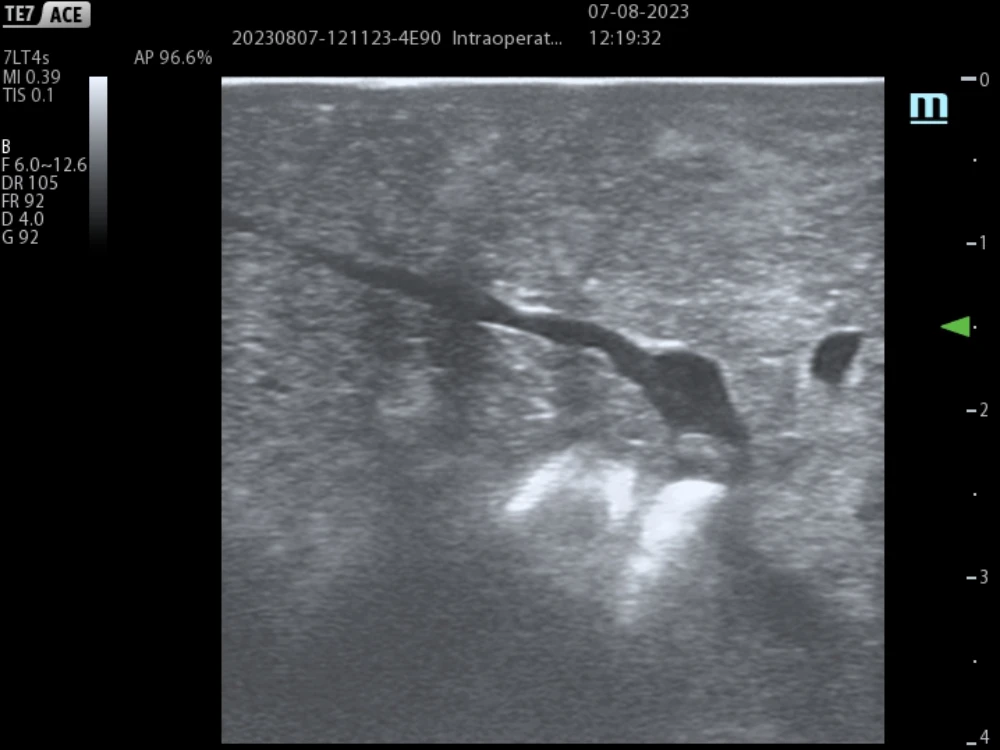

The patient underwent a right hepatectomy. In the transoperative period, we used intraoperative ultrasound with Mindray´s linear T-Shape probe 7LT4s ( Figure 3) and TE7 portable ultrasound system to mark the transection line just at the level of the middle suprahepatic vein, taking care to preserve the material used for suprahepatic venous deprivation (Figure 4 and 5).

non-crirrhotic-liver-fig5

Figure 5. Intraoperative ultrasound embolization material in right suprahepatic vein.